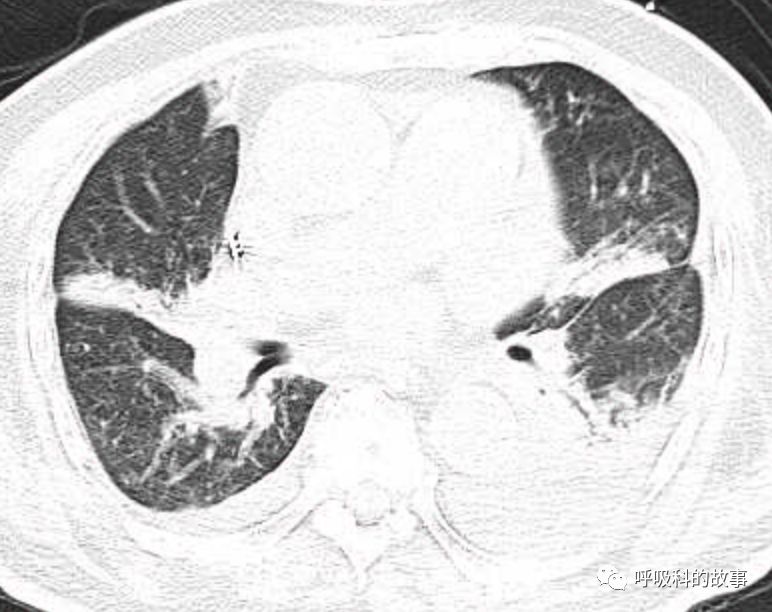

肺部CT如下:

以上的CT给我第一眼的感觉是肺炎,再结合患者有发热和血炎症指标明显增高,肺炎的诊断应该没有问题,但是胸水又是漏出液,结合脑钠肽增高和患者有胸闷气急的症状,心功能不全的诊断也能成立。在某些层面,肺部实变影以内中带为主,还要考虑肺水肿的诊断。入院后给予患者美罗培南抗感染、托拉塞米利尿治疗,以及化痰、雾化处理,患者体温在入院后三天就正常了,入院第五天复查NT-proBNP3390pg/ml;血常规示白细胞 13.5*10^9/L,中性粒细胞81.8%,淋巴细胞13.2%,超敏C-反应蛋白 25mg/L;电解质示钠 160mmol/L,氯 111mmol/L 。虽然炎症指标和心功能指标均有好转,但患者却仍旧精神差,每次查房时仍然表现嗜睡状,家属也反映患者不论白天还是夜晚多数时间不是太清醒。那么问题出在哪里呢?